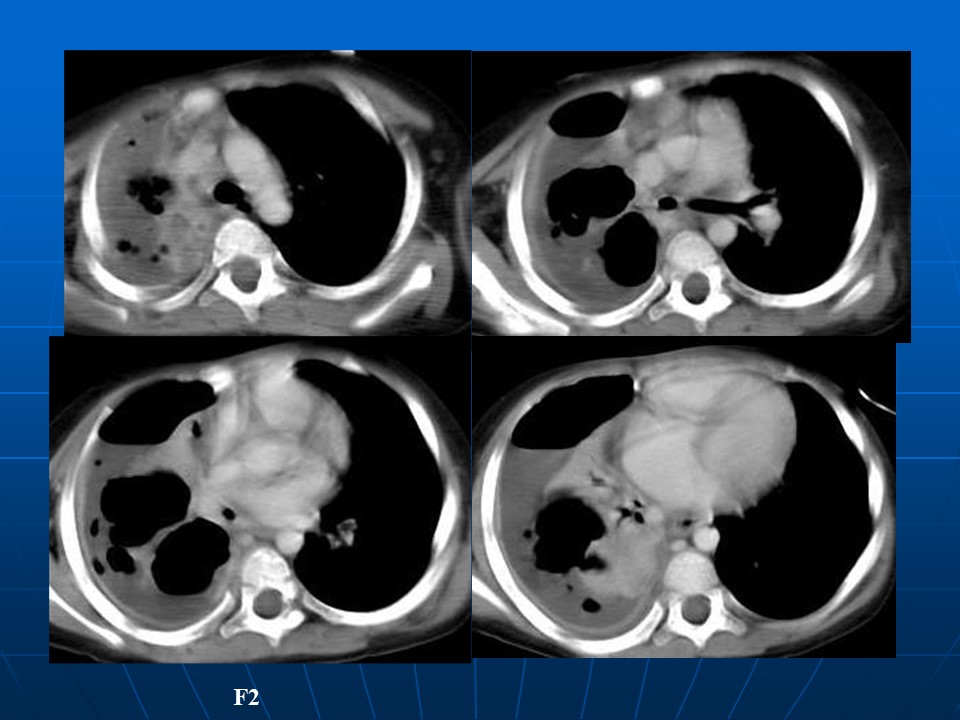

【PPT】肺部炎症新认识点滴